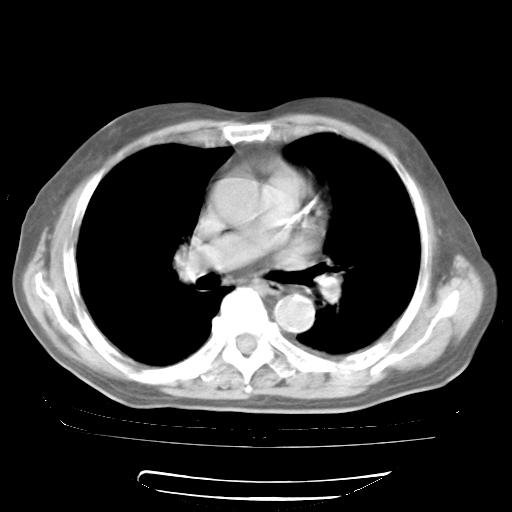

4月28日肺部CT——再次出现类似去年5月9日——透光度降低,“间质性”改变。

4月28日肺部CT——再次出现类似去年5月9日——磨玻璃样、间有“粟粒样”改变。